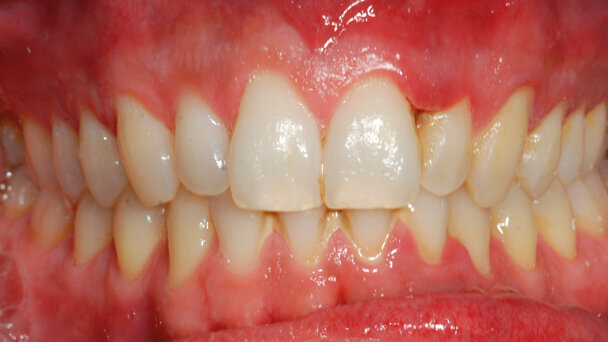

Eseguita l’anamnesi, si procede con un’accurata ispezione del cavo orale che mostra come gli indici parodontali (PI, GBI, sondaggio parodontale) siano entro i limiti della norma così come la salute generale dello stesso, a eccezione della papilla tra gli elementi 1.2 e 1.3, che presenta gli unici siti con un sondaggio patologico (6 mm); come si evince dalla foto frontale pretrattamento (Fig. 1), appare decapitata, completamente disepitelizzata e con abbondante presenza di una pseudo membrana bianco-grigiastra facilmente asportabile (Fig. 2). Quest’ultima, grazie ad analisi di laboratorio sulla qualità batterica presente, porta alla diagnosi di gengivite ulcero-necrotica localizzata.

Trascorso un mese il paziente è ritornato in studio per il secondo controllo, la situazione era decisamente migliorata, la gengiva si presentava ben aderente, tonica e di un rosa corallo (Figg. 6, 7) con assenza di sanguinamento al sondaggio. Permane tuttavia una certa carenza nel volume della papilla interessata come conseguenza del decorso della GUNA.